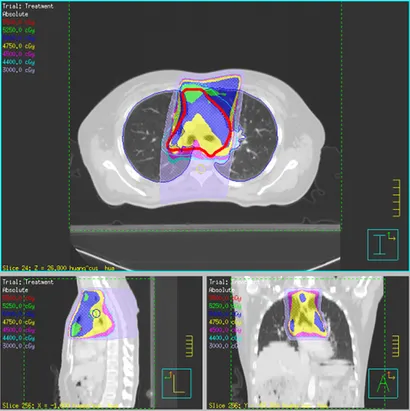

然而2009年7月发现肿瘤转移至右上肺,肿瘤直径为 1 cm,纵隔淋巴结转移。于是接受手术治疗和放化疗。

3 周后开始 DC-CIK 免疫治疗。免疫治疗过程包括以下步骤:首先,从患者身上提取血液,通过血细胞分离器分离和收集单核细胞进行 DC 和 CIK 培养。培养 7 天后,收集成熟的 DC 和 CIK,并以 1:100 的比例混合再培养 7 天。在此期间,进行了无菌试验。细胞存活率保证在 95% 以上。放疗 3 周后开始 DC-CIK 治疗。该治疗方式实现患者13年的长期生存,并且无复发或转移。综上可见,放化疗联合DC-CIK免疫治疗对转移性鼻咽癌具有良好的治疗效果。DC-CIK免疫疗法有效提高患者生存率2024年12月20日,国内研究人员在《转化医学杂志》发表了一篇题为:Combined immunotherapy with dendritic cells and cytokine-induced killer cells for solid tumors: a systematic review and meta-analysis of randomized controlled trials的论文,文中报告了DC-CIK免疫疗法治疗实体瘤显示出有希望的疗效。